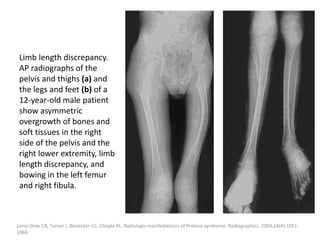

Endovenous ablation techniques

Endovenous ablation techniques like endovenous

laser ablation (ELVA) or endovenous

radiofrequency ablation (ERFA) were successfully

used to close large embryonic venous channels

such as the lateral marginal vein in patients with

Klippel-Trenaunay syndrome (KTS).